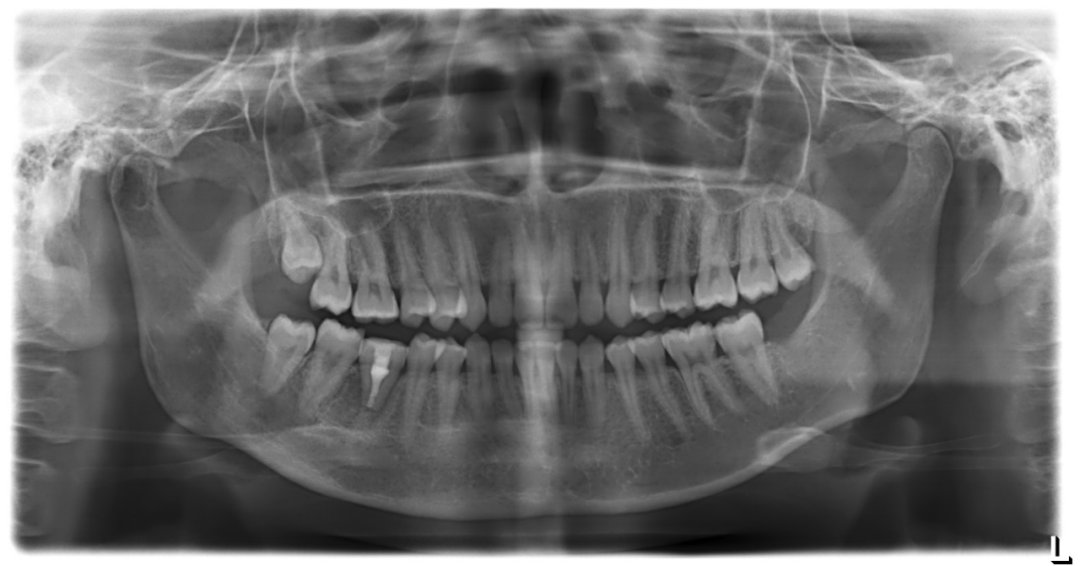

术前照片

术后照片